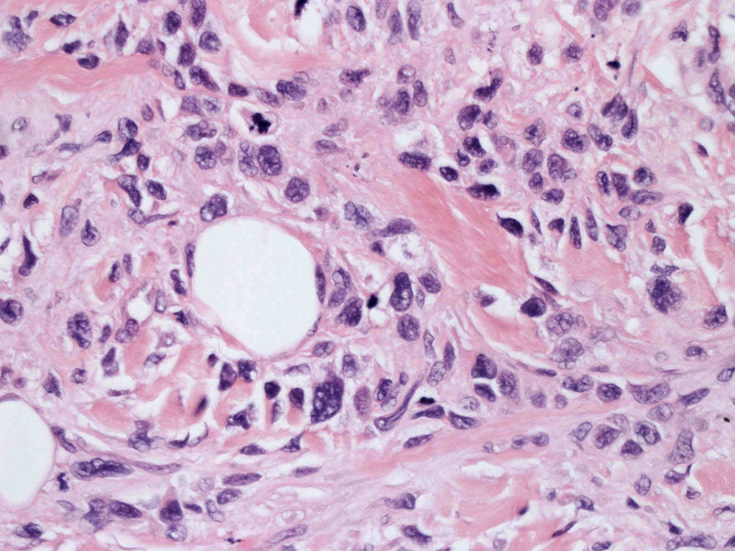

大型細胞の増殖よりなる腫瘍。縦溝,しわ,切れ込みのある核をもった大型細胞も出現する。クロマチンは顆粒状で核小体も明瞭である。核分裂は >50/10hpfと多い。eosinophilsは少ない。壊死が多発することがある。未分化ないし低分化な細胞像, 組織所見のため鑑別診断は多岐にわたり、的確な免疫染色を行う必要がある。

皮膚に異型細胞の浸潤がみられる。異型細胞は表皮内に浸潤するほか、表皮真皮境界部, 真皮, 皮下脂肪組織にもびまん, 結節様の浸潤所見を示す。血管周囲に浸潤、集蔟する所見も多く見られる。 増殖浸潤細胞の核には類円形や腎臓形, またはへこみ, 切れ込み, 溝などを有する多型な核が認められる。クロマチンは粗でvesicularな核が多い。核小体の明らかな核もある。好エオジン性の核内封入体様構造も少数に見られた。mitosisは容易に認められる。hyperchromaticな多型核, bizzarreな細胞が高頻度に認められ異型度は高いと考えられる。細胞質は境界不明瞭, 淡明または泡沫様の 好エオジン性胞体である。